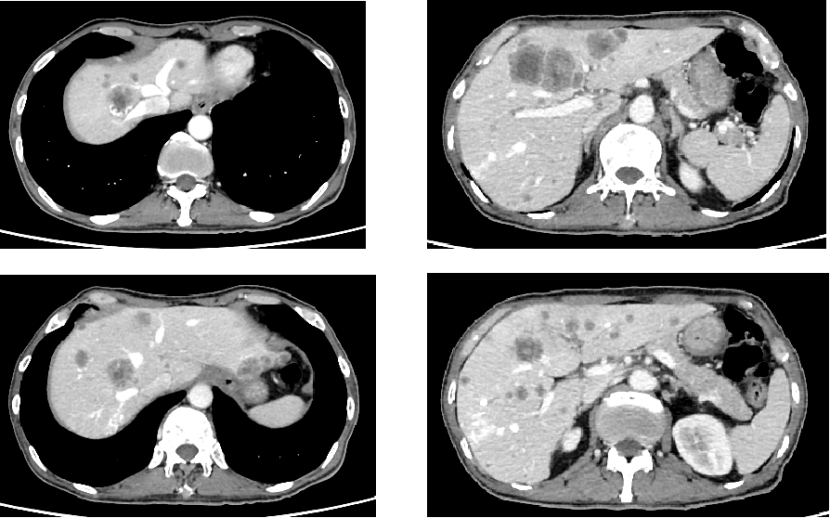

三线治疗(2024年7月起)

• 白蛋白紫杉醇+卡铂+替雷利珠单抗治疗2周期(2024年7月19日、8月9日),Ⅲ度骨髓抑制(白细胞、血红蛋白下降),故白蛋白紫杉醇+替雷利珠单抗维持治疗2周期(2024年8月30日、10月10日),因肝转移,期间联合局部介入治疗(经肝动脉DSA+TACE,2024年9月4日、10月12日)。治疗期间患者骨髓抑制严重,精神萎靡,体重下降,ECOG评分2分。

• 疗效评价:PD。

• 影像学:增强CT(2024年11月8日):肝脏多发转移灶较前增多、增大,病灶仍有活性。

image.png